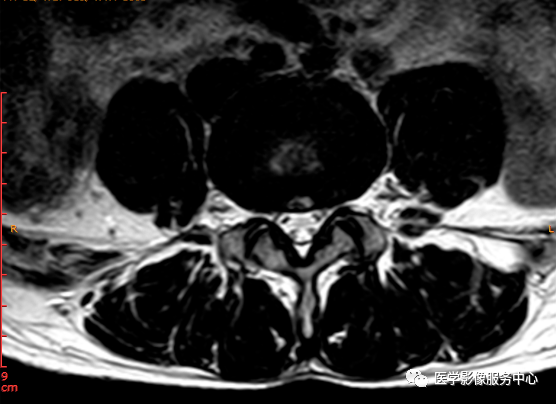

T2轴位

这个患者腰椎间盘膨出程度不明显,神经根没有明显的受压,椎管未见明显狭窄,那这个患者腰疼的“罪魁祸首”是腰椎间盘膨出嘛?

L3-4椎间盘后缘可见点状高信号区(红色箭头所指处)

红色箭头所指的异常信号区是是什么呢?平时工作中大家有没有遇到这种情况,你会不会忽略这个异常信号?有没有想过这个椎间盘后缘高信号区是引起患者腰疼的重要因素呢?下面为大家重点介绍。

影像表现主要在T2矢状位及T2横断位可见椎间盘前缘或后缘可见高信号区;

日常工作因腰腿疼痛来检查腰椎MRI的很多,而腰腿疼痛并不一定就是腰椎椎间盘突出或膨出导致的,我们应该需要知道椎间盘HIZ也会引起腰腿疼痛,这种椎间盘源性的疼痛我们不能“忽略”;椎间盘后方HIZ并不少见,椎间盘后方 HIZ 在 T2WI 的局限性高信号、T1WI 呈局限性较低或等信号意味着通常所指的纤维环破裂伴随肉芽组织长入;而 T1WI、T2WI 均呈高信号可能是钙化组织。